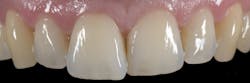

I chose Variolink Esthetic LC (neutral) for the cementation procedure. Thanks to its new high-viscosity formula, the material is now even easier to handle. It can be applied with accuracy and stays in place without spreading uncontrollably (figures 8, 9). Once the veneer is correctly placed on the tooth, you can feel a slight resistance (tactile feedback). I placed the veneer using an OptraSculpt Pad, performed a brief tack cure, and then removed excess cement with dental floss (figures 10, 11). This was followed by final light curing (Bluephase PowerCure, Ivoclar). To prevent the formation of an oxygen inhibition layer at the restoration margins, I covered the cementation joint with glycerine gel Liquid Strip before the final cure (figures 12, 13).

A follow-up examination was performed 10 days after the placement. The tooth structure had rehydrated during that time, allowing me to assess whether the veneer had integrated successfully. The patient and I were both very pleased with the esthetic result. The visual impression of the anterior front is beautiful and harmonious. The dainty veneer looks completely natural and unnoticeable (figure 14).